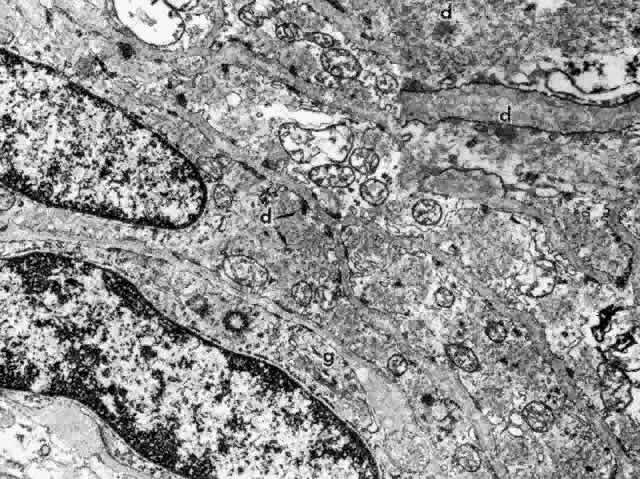

The ultrastructure of the ciliary muscle fibers resembles that of smooth muscle elsewhere, with a few interesting differences. The muscle bundles are surrounded by a sheath of flattened fibrocytes rather than primarily by collagen fibers (Fig. 37),46–48 showing that they belong to the multiunit family of smooth muscles instead of the syncytial family.49 Each fiber is covered by a continuous basement membrane and has many pinocytotic vesicles or caveolae on the plasmalemmal membrane. The fiber is filled with 60- to 70-nm myofibrils that show the usual attachment densities among them, as well as focally where they attach to the basement membranes (Fig. 38). These myofibrils are the intermediate filaments of the cell and contain the protein desmin, used to identify smooth or skeletal muscle cells by immunohistochemistry. A less specific protein, smooth muscle actin, is also present but characterizes myofibroblasts as well. Mitochondria and endoplasmic reticulum are more numerous and Golgi apparatus better developed than in most smooth muscle cells. Occasional desmosomes interconnect the cells but no gap junctions. Studies of muscle enzymes have suggested that there may be functional differences between the longitudinal muscle and the radial-circular muscle complex.50 The longitudinal muscle cells, particularly their anterior tips, are heavily fibrillar with fewer mitochondria than the other muscles and have enzyme characteristics somewhat like those of skeletal rapid twitch fibers. It is hypothesized that their multiunit structure might allow the muscle tips to react first in accommodation, stiffening them to counteract the posterior pull of the remaining muscle on the scleral spur.

Fig. 38. Elongated radial muscle fibers surrounded by basement membranes have large mitochondria, Golgi apparatus (g), and many central and peripheral densities (d). (X 21,400) Inset. The plentiful smooth muscle myofibrils in the cytoplasm attach to the densities in both central and peripheral locations (d). (X 70,000)